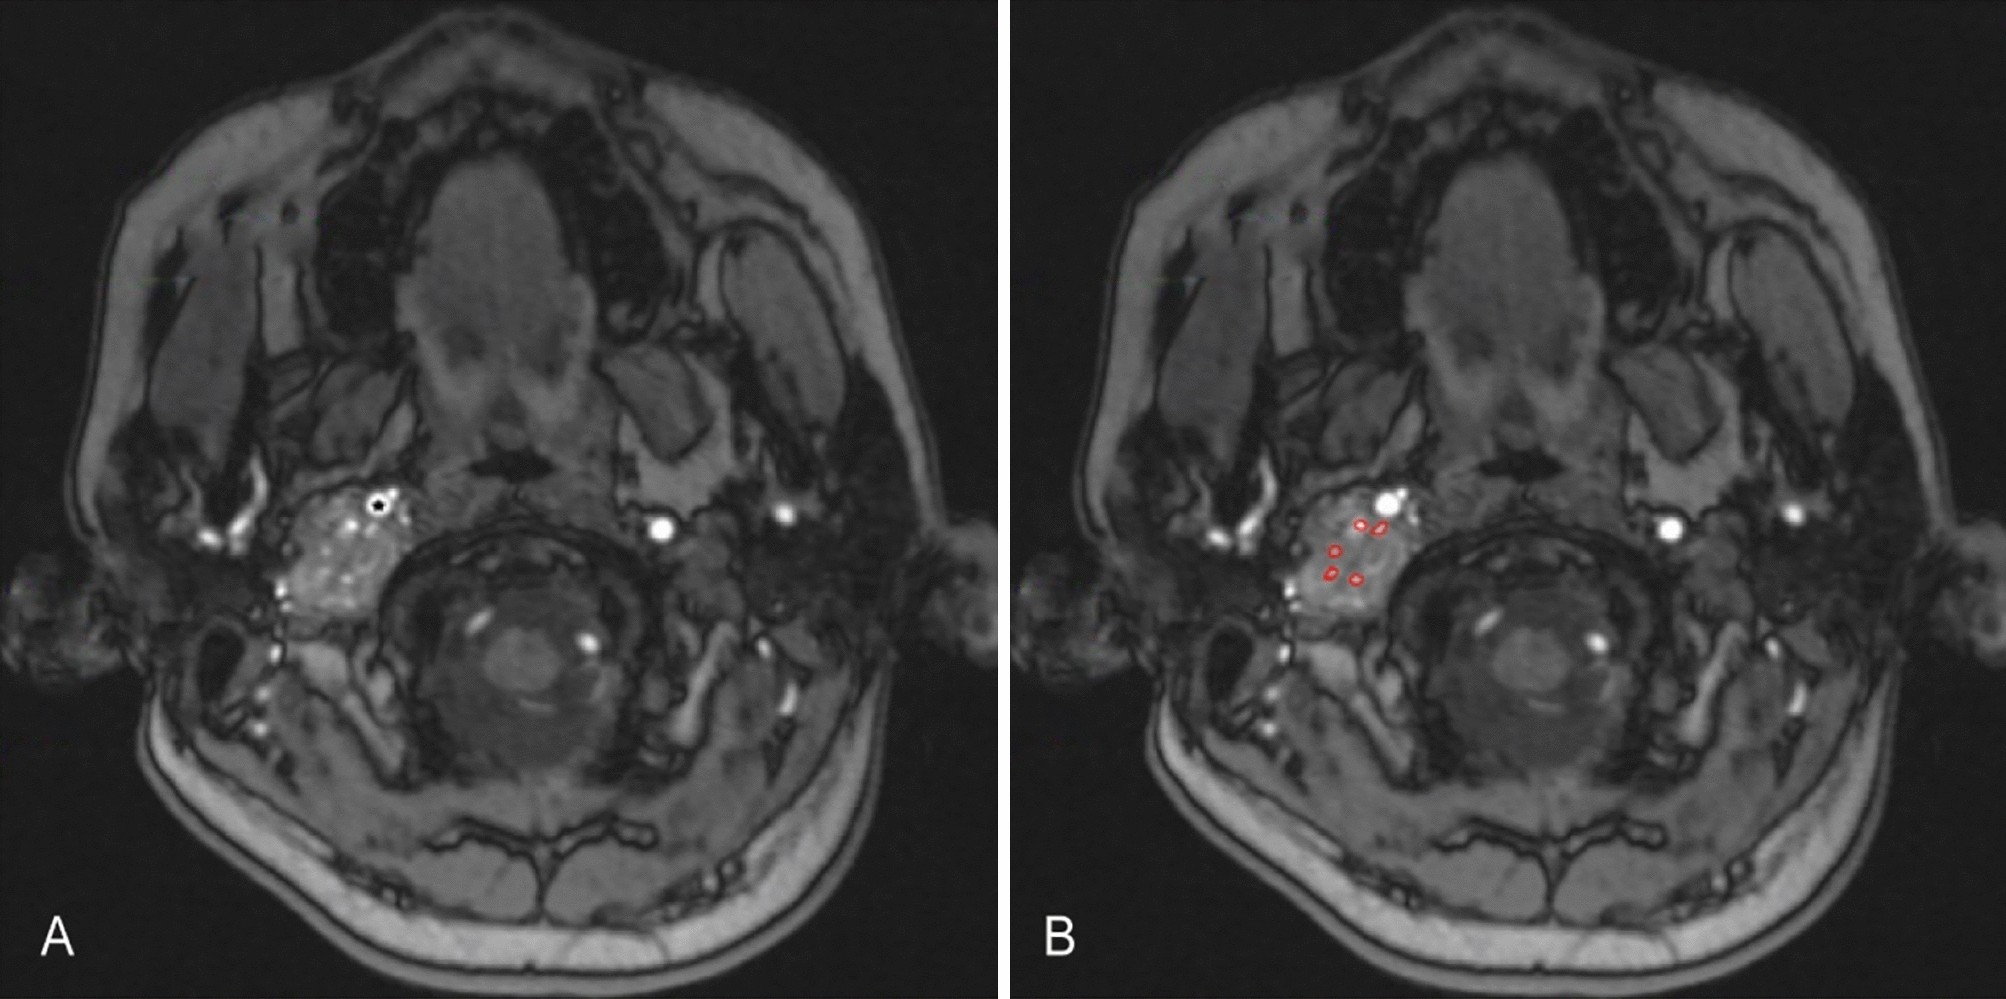

Figure 1

The preoperative axial MRA image of patient with C3 JPs on the right. There are multiple intratumor blood vessels and intraoperative blood loss was 600 ml. (A) The black star indicates the internal carotid artery. (B) The red areas represent the maximum cross-sectional area of intratumor blood vessels.